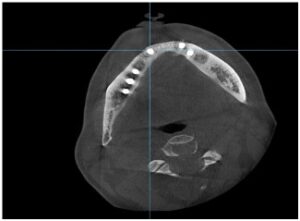

양산수면치과 에이디중부치과에서는

임플란트 식립을 진행하기 전

파노라마 사진과 3D CT 사진 촬영을 통해

위턱의 경우 상악동과의 거리,

아래턱 하방으로 지나가는

하치조 신경관의 위치,

잔존 치조골의 양과 두께,

눈에 보이지 않는 해부학적 구조물 등을

면밀하게 확인하는 과정을 거쳤으며,

이러한 결과를 토대로

임플란트를 식립하기 좋은 위치를 선정하고

식립 될 Fixture의 굵기와 길이,

식립 방향 등을

컴퓨터 분석과 시뮬레이션을 통해

미리 파악하는 과정을 거쳤는데요.

이러한 과정 덕분에

구강 내에서 더욱 빠르고 안전하게

식립을 도와드렸으며

파노라마 촬영을 통해

임플란트가 정확한 위치와 방향으로

식립 된 것을 확인하였습니다.